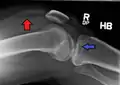

Lipohemarthrosis (presence of fat and blood from bone marrow in the joint space after an intraarticular fracture) seen on X-ray in a person with a subtle tibial plateau fracture

Lipohemarthrosis due to a tibial plateau fracture